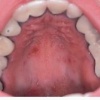

Maakaartkeel

(lingua geographica)

– Ebakorrapäraseid punaseid atroofilisi limaskestalaike ümbritsevad matsereerunud filiformsete papillide poolt moodustatud hallikad vallitaolised piirkonnad. – Laigud muudavad iga päev kuju. – Ohutu leid, millega ei kaasne haigusnähte.